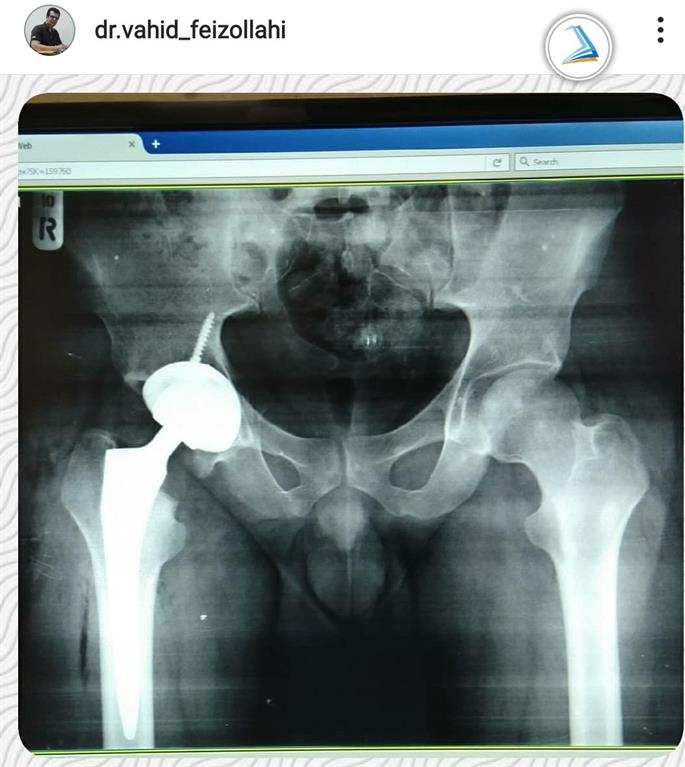

2. A 33-year-old man

A 33-year-old man with femoral head osteonecrosis that lead to limited hip range of motion and severe pain while walking and standing was treated with complete hip replacement surgery and was launched on the day after the surgery.